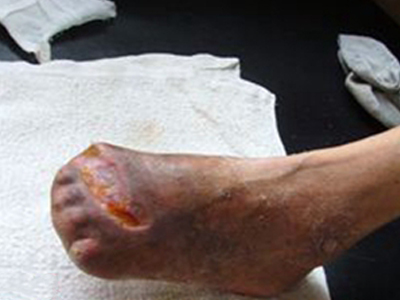

血栓闭塞性脉管炎又称Buerger病,是一种以中、小动脉节段性,非化脓性炎症和动脉腔内血栓形成为特征的慢性动脉闭塞性疾病。主要侵袭四肢,尤其是下肢的中、小动脉和静脉,引起患肢远侧段缺血性病变,出现肢体疼痛、皮肤颜色改变以及坏疽等症状。

血栓闭塞性脉管炎早期肢体发凉、怕冷,逐步出现肢体皮温下降,也可以出现肢体针刺感、烧灼感和麻木等感觉异常。因肢体缺血导致皮色苍白,还可出现皮肤潮红或青紫等表现。患肢还可出现游走性浅静脉炎症状。

肢体缺血可引起程度不同的皮肤干燥、脱屑、患肢肌肉萎缩、肢体变细等。肢端动脉搏动减弱或消失,肢体缺血的最严重后果为肢端坏疽或溃疡。